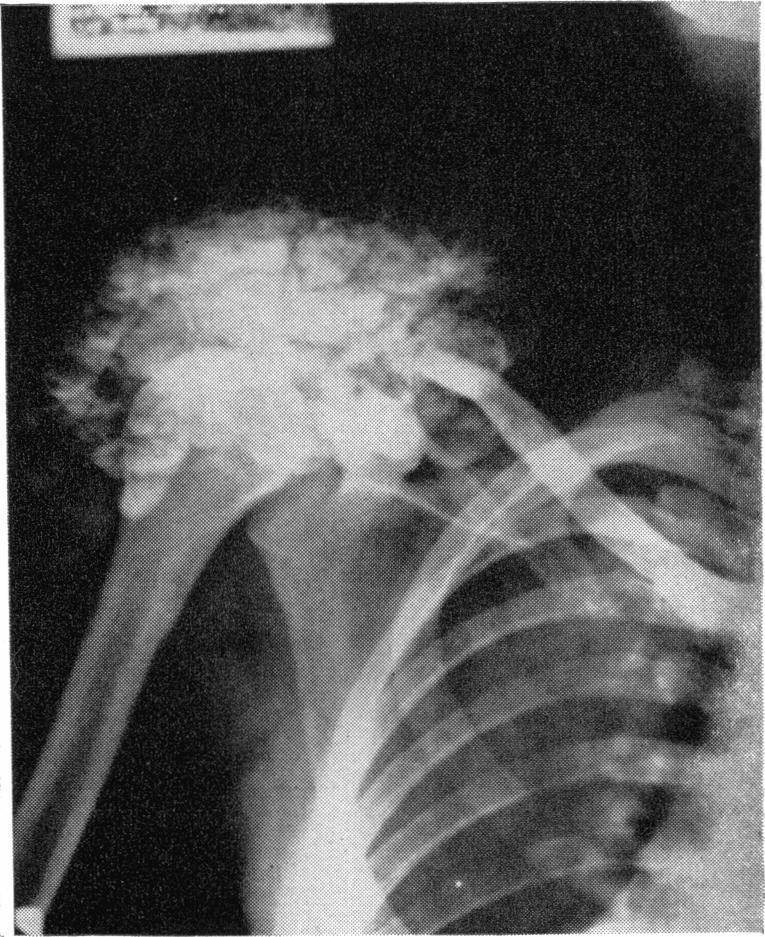

OCCULT HYPERPARATHYROIDISM AND THE RAPID CALCIUM INFUSION TEST.

Bull N Y Acad Med. 1964 Mar;40(3):188-203.